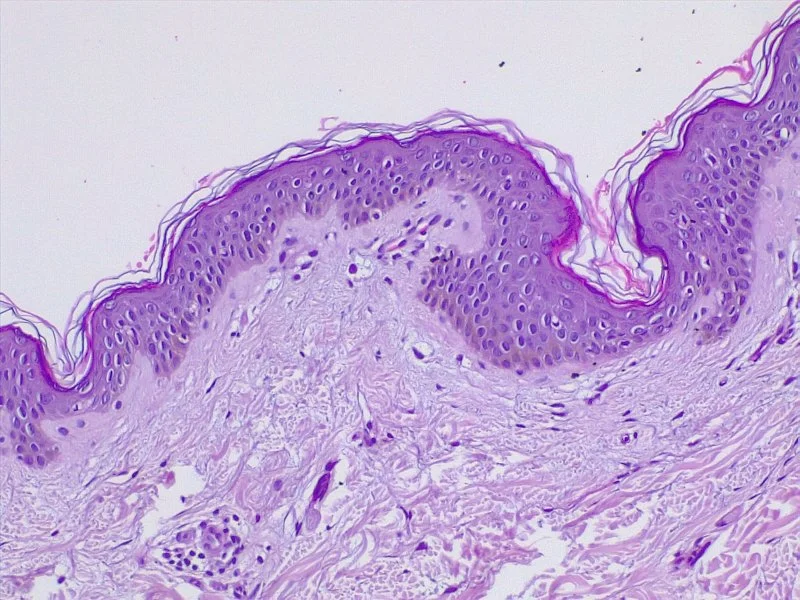

Nuestra piel es un órgano y como tal debe ser tratada. En Cumbres, ofrecemos tratamientos innovadores y modernizados para el cuidado de la piel para obtener resultados óptimos. Bajo un concepto de reparación de la piel, y tratamiento de afecciones específicas de cada tipo de piel. EN CUMBRES CONSIDERAMOS QUE TRABAJAR EN UNA PIEL SALUDABLE SERÁ EL LIENZO DE LA MANO DE LOS PROCEDIMIENTOS. NUESTRO ENFOQUE ES PROACTIVO, PREVENTIVO Y PERSONALIZADO.

Los planes de tratamiento diseñados para la restauración de la piel se personalizan para cada paciente de acuerdo con la salud y las preocupaciones de su piel. Este enfoque único abarca todos los tipos de piel, géneros y edades y es especialmente excelente para tratar afecciones de la piel que pueden ser difíciles de tratar o que no responden a los tratamientos convencionales. Los tratamientos suelen ser sencillos y eficaces. Durante tu consulta inicial evaluaremos el estado actual de tu piel y determinar el mejor curso de tratamiento posible para brindar resultados óptimos.

Restaurar la salud de tu piel es un proceso a largo plazo que es tanto correctivo como preventivo. LO QUE NOS DIFERENCÍA ES LA INDICACIÓN Y PLANES DE TRATAMIENTO BASADOS EN LA EVIDENCIA DE GRADO MÉDICO Y ROTACIÓN A MEDIDA QUE TU PIEL CAMBIA CON TU ESTILO DE VIDA Y EDAD.